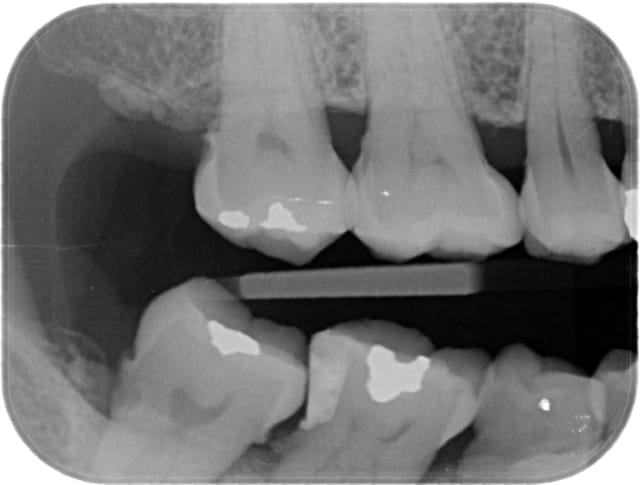

Patiente la cinquantaine, ne parlant pas français, avec DDM++, tartre, hygiène médiocre, et comme vous le voyez des caries très mal placées entre le son tartre et ses lésions infra-osseuses.

Comme vous le voyez sur la deuxième radio j'ai essayé de bidouiller mais le résultat est crade (en plus y a encore du tartre !) et non satisfaisant.

Sur l'aspect restauratif, que peut-on proposer de viable (en dehors de extrac implants) sur ce genre de cas ?